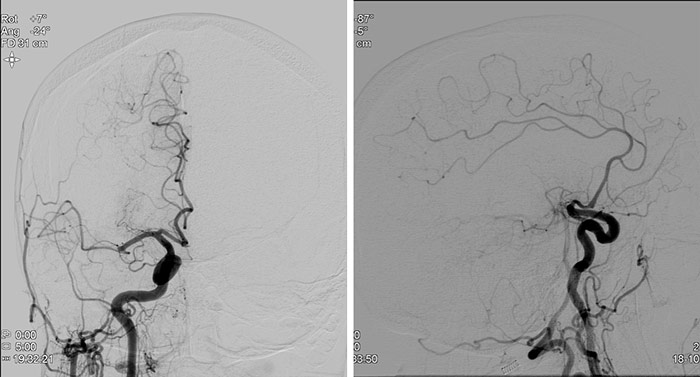

A quick case on Monday morning. Thrombus in the transition zone between M1 and M2.

#ADAPT with Sofia 5 FR.#thrombectomy@YoungNIR@LINNConline@ESOstrokepic.twitter.com/1nx2Bn3gX4